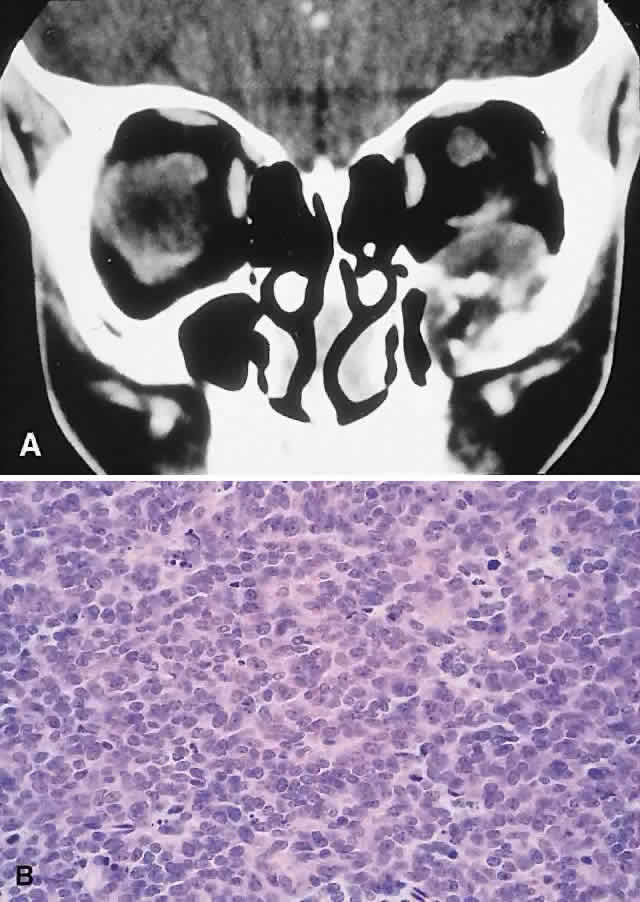

IMAGING. The CT appearance is of an expansile or permeating mass that shows mottled bone destruction (Fig. 11). There may be an associated soft tissue component.

Fig. 11. This 12-year-old boy experienced subacute left proptosis, vertical globe displacement, and lower lid edema. A. CT showed an expansile mass with mottled bone destruction of the orbital floor. B. Biopsy revealed a Ewing's sarcoma consisting of densely packed and mitotically active small round cells (hematoxylin-eosin, × 80).

HISTOPATHOLOGY. The tumor consists of firm, white tissue made up microscopically of sheets and clusters of uniform, small round cells. Cytoplasmic glycogen, as demonstrated by periodic acid-Schiff (PAS) positivity, is present in 90% of cases. Ultrastructurally, there is evidence of glycogen and a sparsity of organelles.18